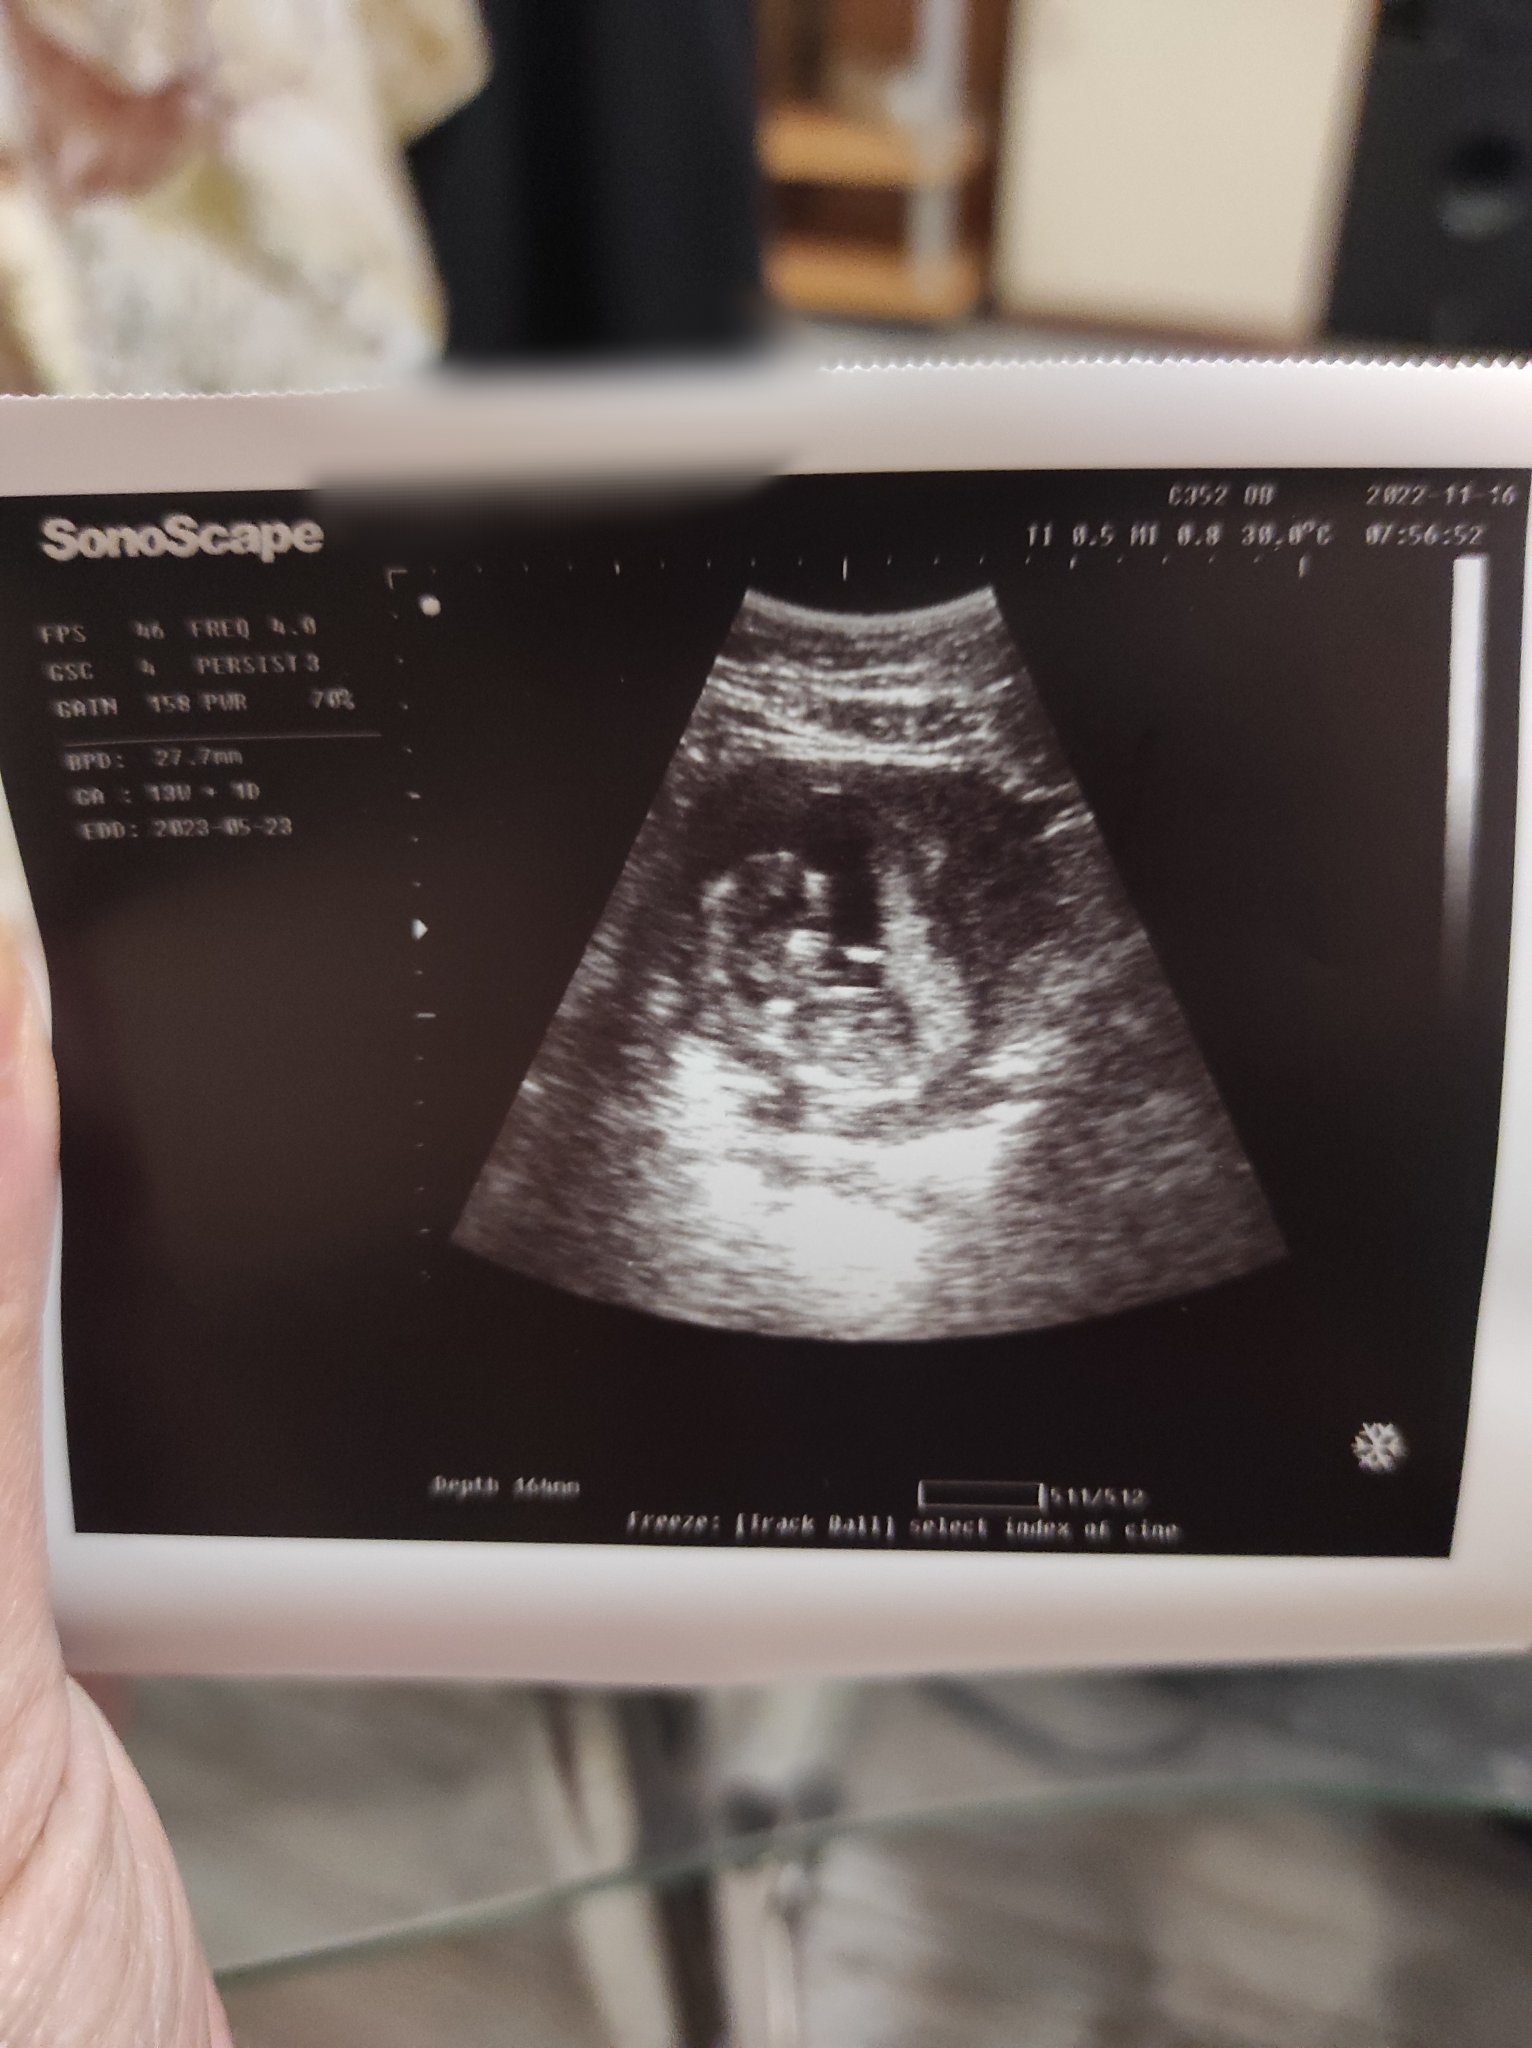

Мами за пореден път пиша ,днес отново бях на преглед .

Но докато ме гледаше каза само -още 12 седм и млъкна .

Разпитах го как са нещата вика до ре и съм била в началото на 14 седм.

Как ви се струва снимката ?

И възможно ли е да ми е дал друга снима на друга жена ??

Знае,че съм страхлива и мн притеснителна дали не ми спестява нещо -затова казвам снимката ..ако разбирате да ми кажете .

И ако недай си боже има нещо трябва ли веднага да каже знам ,че е опасно за майката ако се случи лошото ?

Ако разбирате помогнете ако не подминете .

И часа ми направи впечатление понеже бях по късно ..и все пак възможно ли е да ми е дал чужда снимка ?

И ако бебето ми не е ок веднага ли трябва да ми каже .

вие сте в 13!г с 1 ден според снимката .Бебо направо те гледка от снимката право в очите с неговите очички и е дълго почти 3 см. От снимката, гледам, че му е удобничко и му е добре сега.

Чул те Господ ,доктора спомена още 12 седм и млъкна .

Ембриона в 13 гс не е почти 3 см, моля ви….. bpd което според вас е дължината, е само обиколката на главичката. Спрете с грешната имформация. А вие Гери отидете на друг гинеколог, който ще ви дава повече обяснения. На снимката в дясно пише часа, снимката едва ли е на друга жена